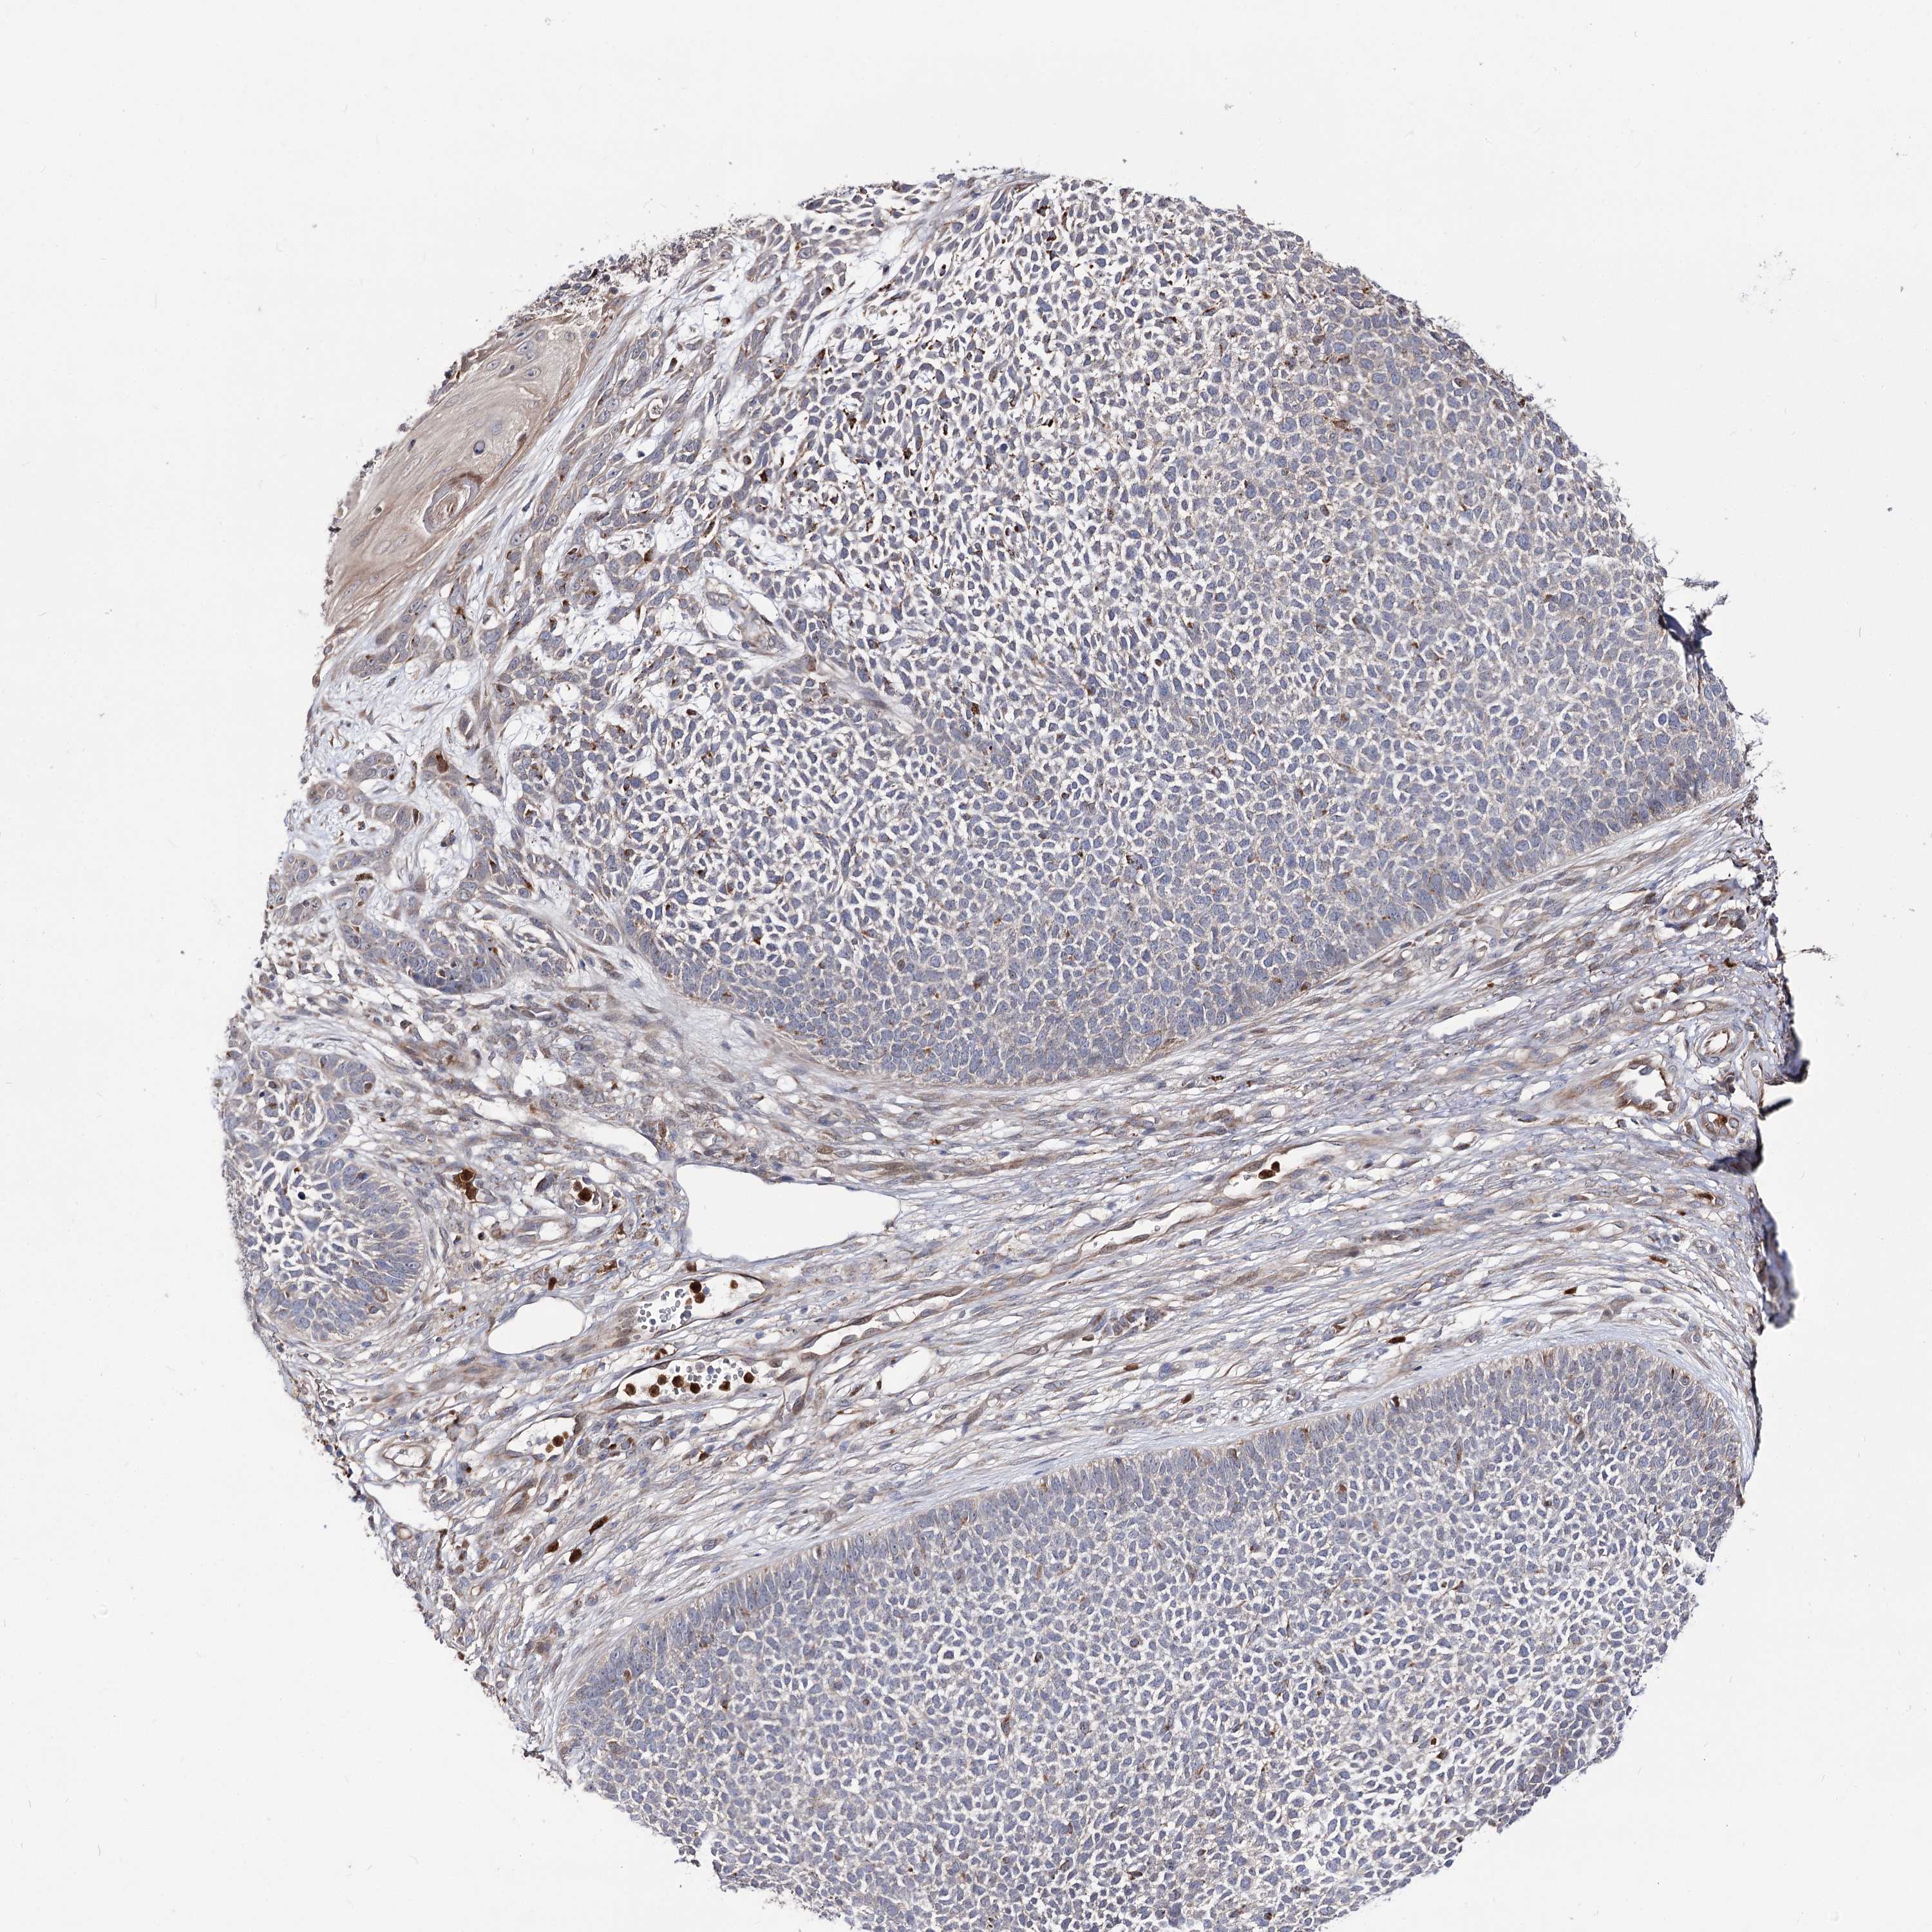

Basal cell and squamous cell cancer

SKIN CANCER - Protein expressioni

A mouse-over function shows sample information and annotation data. Click on an image to view it in a full screen mode. Samples can be filtered based on level of antibody staining by selecting one or several of the following categories: high, medium, low and not detected. The assay and annotation is described here.

Antibody stainingi

Antibody staining in the annotated cell types in the current human tissue is reported as not detected, low, medium, or high, based on conventional immunohistochemistry profiling in selected tissues. This score is based on the combination of the staining intensity and fraction of stained cells.

Each image is clickable and will lead to virtual microscopy that enables deeper exploration of all samples and also displays staining intensity scores, fraction scores and subcellular localization as well as patient and tissue information for each sample.

Antibody HPA038040

Staining

High

Medium

Low

Not detected

Intensity

Strong

Moderate

Weak

Negative

Quantity

>75%

75%-25%

<25%

None

Location

Nuclear

Cytoplasmic/membranous

Cytoplasmic/membranous,nuclear

Basal cell carcinoma